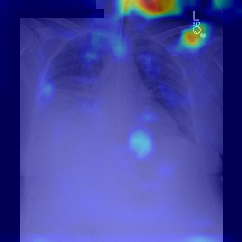

Fig.Β 5: Examples of class activation maps of positive cases. Left to right: image with annotation in blue, no L1 regularization, with L1 regularization, baseline.

Fig. 5 shows examples of class activation maps of positive cases for visual comparisons among the final models. These were produced using the Grad-CAM approach [14]. The images were annotated by an expert for the regions of opacity. Although all models correctly classified the cases as positives, the activation maps of the baseline model were barely correlated with the annotated regions, with more irrelevant hot spots outside the lungs. On the other hand, the activation maps of the models with feature selections were better correlated with the annotation. In other words, these smaller networks seems to be also more focused on the correct regions, which is a step towards explainability. The image in the third row shows that the VGG16 activation map has important components outside the lungs, focusing on English characters on the image. Whereas the reduced networks show more activation in marked areas of the lungs.